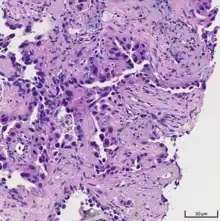

Histopathology of lepidic predominant adenocarcinoma.

• lepidic predominant [18]

Cell patterns identifying subtypes are associated with prognosis, ranging from favorable (lepidic) to intermediate (acinar and papillary) to poor (micropapillary and solid).[2]

Adenocarcinoma of the lung tends to stain mucin positive as it is derived from the mucus-producing glands of the lungs. Similar to other adenocarcinoma, if this tumor is well differentiated (low grade) it will resemble the normal glandular structure. Poorly differentiated adenocarcinoma will not resemble the normal glands (high grade) and will be detected by seeing that they stain positive for mucin (which the glands produce). Adenocarcinoma can also be distinguished by staining for TTF-1, a cell marker for adenocarcinoma.[29]

As discussed previously, the category of adenocarcinoma includes are range of subtypes, and any one tumor tends to be heterogeneous in composition. Several major subtypes are currently recognized by the World Health Organization (WHO)[1] and the International Association for the Study of Lung Cancer (IASLC) / American Thoracic Society (ATS) / European Respiratory Society (ERS):[30][31][32] lepidic predominant adenocarcinoma, acinar predominant adenocarcinoma, papillary predominant adenocarcinoma, micropapillary predominant adenocarcinoma, solid predominant adenocarcinoma, and solid predominant with mucin production. In as many as 80% of these tumors, components of more than one subtype will be recognized. Surgically resected tumors should be classified by comprehensive histological subtyping, describing patterns of involvement in increments of 5%. The predominant histologic subtype is then used to classify the tumor overall.[2] The predominant subtype is prognostic for survival after complete resection.[33]